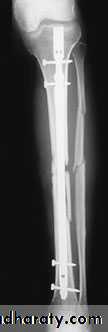

IMN